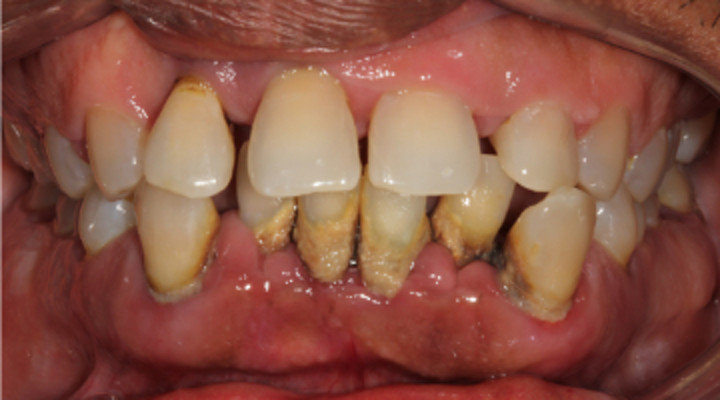

What are the different stages of periodontal disease?

Four stages of periodontal disease

Periodontal disease is broken up into four different stages, which include:

Gingivitis: This is the only stage of the disease that is reversible as it hasn’t attacked the bones yet. This is a result of plaque buildup around the teeth. Bleeding gums is one of the first symptoms you may experience. However, most symptoms of gingivitis are painless, which is what makes periodontal disease so common. Good oral hygiene and regular dental exams and routine dental cleanings can help treat and reverse gingivitis successfully.

Slight Periodontal Disease: Slight periodontal disease is the second stage of gum disease. It isn’t reversible, but can be managed. Once you reach stage two, the infection has spread to the bone and has begun to destroy bones. The bacteria have become more aggressive, which is what leads to bone less. Scaling and root planing can be used to deep clean the teeth gums. It removes deposits of bacteria that are deeply rooted in your gums.

Moderate Periodontal Disease: The third stage of periodontal disease has more probing depths, which allows for even more bacteria to attack the bones and the blood stream, too. Much like slight periodontal disease, our professional specialists will use scaling and root planing to thoroughly clean the area.

Advanced Periodontal Disease: The final stage of periodontal disease is when the infection has evolved into disease-causing bacteria. It can cause redness, swollen gums that ooze pus, sensitivity, loosening of teeth, painful chewing, severe bad breath, and bone loss. This stage requires periodontal surgery or laser therapy with the PerioLase MVP-7 TruePulse to clean the deep bacteria-filled pockets. If left untreated, stage four can lead to gaps or spacing between the teeth, the need for dentures, gum recession, and other serious health problems.